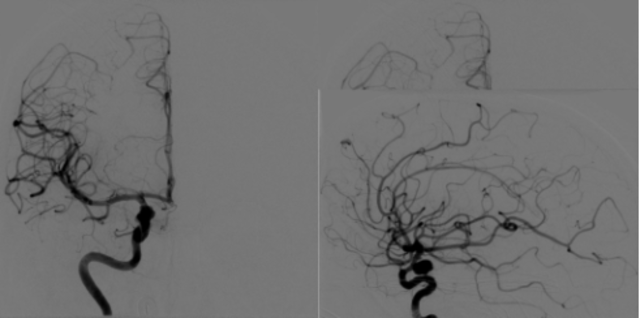

• Angiografia

Angiografia

-Inventor: Antonio Caetan de Abreu.

-es el estudio de los vasos sanguíneos que no son visibles mediante la radiología convencional.

-se crea la Angeografia digital

-se crea la Angiografia con substraccion digital y reconstruccion digital